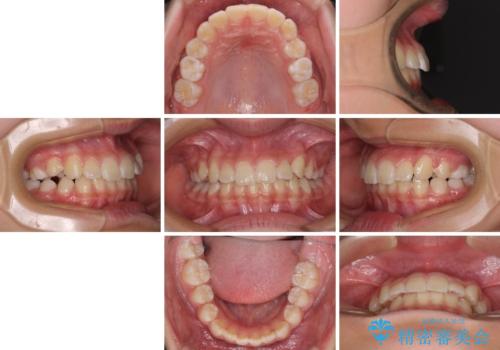

今後残っている乳歯が抜け、永久歯が萌出してくるため、調整可能なリンガルアーチを用いて保定を行っています。

12歳臼歯が萌出するまで経過観察を行い、すべての歯が萌出した後に、全顎矯正治療(Ⅱ期治療)を行っていきます。